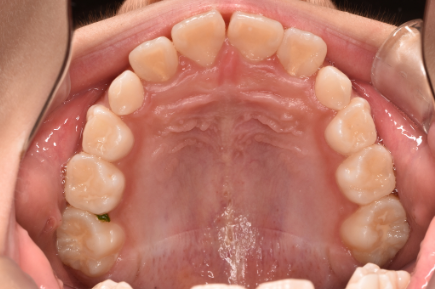

治療前

| カウンセリング・診断結果 | お口の中を確認したところ、左側の前歯の一部(側切歯/B)のかみ合わせが上下反対になっていました。 矯正治療のための精密検査を行った結果、骨格に大きな問題はありませんでした。そのためご相談にあった前歯のガタガタに関してはスムーズに矯正を進めることができると判断しました。 ただ、犬歯(C)が生えている状況(萌出状況)を見ると今後、永久歯が生えた段階で「永久歯列の矯正(2期治療)」を行う必要性が生まれるかもしれないと考えました。 |

| 行ったご提案・治療内容 | 治療前に「矯正の期間としては1年~1年半かかる」ということと、「乳歯の段階で矯正した後、永久歯が生えた段階でも治療が必要になるかもしれない」ということをお伝えし、理解していただきました。その上で下記の治療計画をご提案しました。 ①まずは、マウスピースとお口のトレーニングで矯正を進める小児向けの治療法「マイオブレース」を実施。正しい呼吸の方法や、舌の使い方、飲み込み方の練習のほか、唇の筋力トレーニングなどで悪い習慣や癖を直します。 ②その後、経過を観察しながら「上顎拡大装置」という機器を使って上顎の骨を拡大する治療を行います。夜間には上顎骨の成長を改善するための「上顎牽引装置」を使用する可能性もあります。 ③最終的にはインビザラインを使用して歯を適切な位置に移動させ、歯並びを整える矯正治療を行います。 以上、説明内容に納得していただいた上で計画通りに治療を進めました。 |